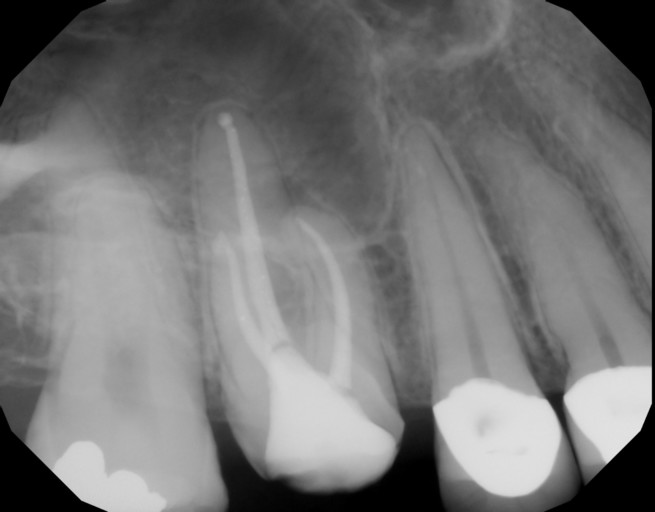

I had a root canal in May. I went to the dentist to fill my tooth and he filled my tooth too much according to my endodontist, she has it on an x Ray that the endodontist took. Now I am on antibiotics

It is possible that over filling a tooth during a root canal can cause inflammation of the periodontal ligament, which results in tenderness and pain.  A small amount of gutta percha or sealer wil be okay, however every person is different as is every tooth.  Healing will be different in each person.  It is best to take the antibiotics as directed and stick to a soft diet until the tooth is healed in order to keep pressure off the tooth.

Does over filling the tooth after a root canal cause inflammation and pain